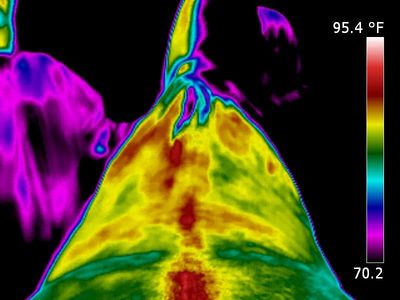

This mare had a pelvis injury in the paddock. Not totally sure what happened. Visually the pelvis on the right sign in the flank region is indented and the pelvis assymmetrical. This was taken approximately 2 months after the injury. There is an extreme difference in temperature and pattern. Heat spots are shown. Also the right stifle region is effected. The view of the pelvis shows the glutues on right side and sacroiliac region is inflammed.

This mare received treatment and was bought back into work slowly. 8months later she had not recovered so she will be a brood mare. Thermal imaging was able to show areas of pain and inflammation.